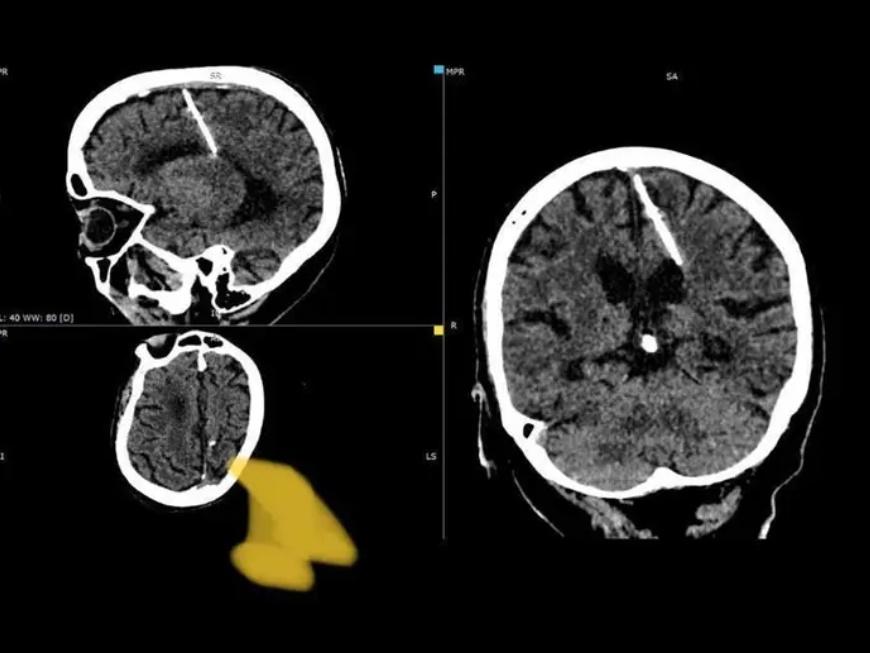

俄八旬婦腦藏3厘米長針,父母竟是疑兇,醫生揭恐怖原因。(Telegram)

綜合報道,庫頁島衞生部周三(4)在社交媒體Telegram發文表示,這名80歲婦女進行腦部X光檢查時,發現大腦左頂葉裡有一支3厘米長的針,幾乎貫穿半個大腦。報道引述醫生指出,該名婦人居於俄羅斯遠東地區,目前仍在接受觀察,那支針亦沒有對她造成任何頭痛或不適,由於因擔心手術會造成婦人健康惡化,因此決定不進行手術將針取出。

據官員表示,這支針從女子出生起就一直藏在腦中,事實上,這是第二次大戰期間,前蘇聯常見的「殺嬰手法」,官員指出,當時正處飢荒年代,有些父母因為沒有糧食養育下一代,因此會將針插進新生兒還未閉合的頭頂囟門,當頭頂囟門閉合後就看不見異物,嬰兒也會死亡,「這種情形在饑荒年代相當普遍」。醫師亦認為,婦人的雙親當初沒有能力撫養她,於是在她還是嬰兒時期就試圖殺害她,將針貫穿她的左頂葉,詎料結果不似預期,婦人得以活下來。